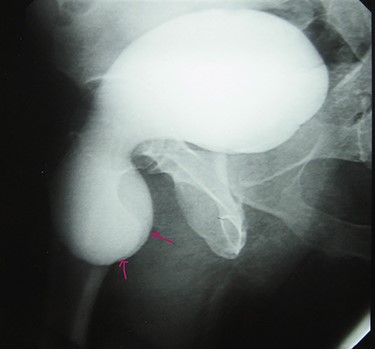

A 72-year-old man with a history of controlled diabetes and hypertension presented to our department with right inguinal swelling and intermittent lower urinary tract symptoms (LUTS) with pollakiuria, dysuria, prolonged micturition time and a sensation of a full bladder after micturition. He reported nausea, vomiting and right lower quadrant paint. The patient also reported having to manually compress the scrotum in order to empty the bladder. Physical examination revealed a slightly painful on palpation and reducible 6 cm right inguinal hernia extending into the right hemiscrotum. The body mass index of the patient was 31.4 kg/m2. His PSA was 4.3 ng/ml. On uroflowmetry, maximum flow rate (Qmax) was 13 ml/s and the voided volume was 180 cc. The uroflow curve was flat. The Bacteriological examination of urine was negative. Retrograde urethrocystography revealed right inguinal hernia containing a portion of the urinary bladder (Figs 1,2). He also had an intravenous urography in order to study the upper urinary tract and to have an idea of the renal function. This radiological exploration confirms the data of the retrograde urethrocystography and illustrates well the bladder hernia. However, a moderate left hydronephrosis with a nonobstructive pyelic calculus of 1.5 cm was observed on intravenous urography (Figs 3,4). Intraoperative findings revealed a direct right inguinal hernia with complete herniation of bladder into the scrotum. The bladder appeared healthy with no signs of injury and was restored to its normal anatomical position without resection. The hernia was repaired with a biologic mesh by the Lichtenstein technique. The patient had an uneventful postoperative course. Concerning his pyelic calculus problem, shock wave lithotripsy sessions were scheduled.

Intravenous urography: nonobstructive pyelic calculus of 1.5 cm.